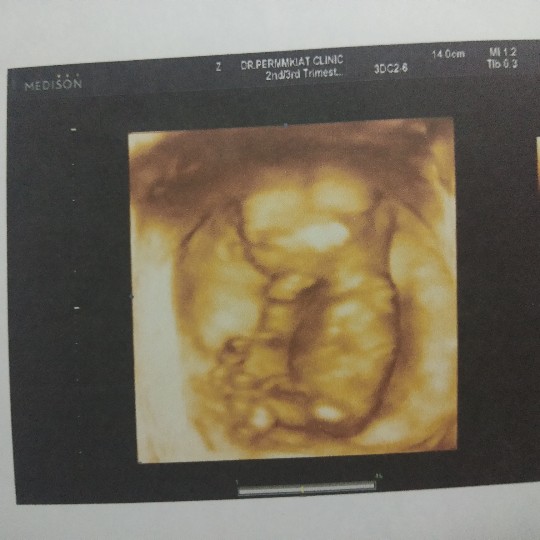

12Wค่ะ

3เดือนแล้วค่ะ..เริ่มเห็นแขน ขา บ้านใหนเหมือนกันมั๊ยค่ะ???3เดือนเห็นชัดขนาดนี้เหมือนกันรึป่าวค่ะ

ของเรา14wค่ะ ไปซาวด์มาเมื่อวาน 😄😄